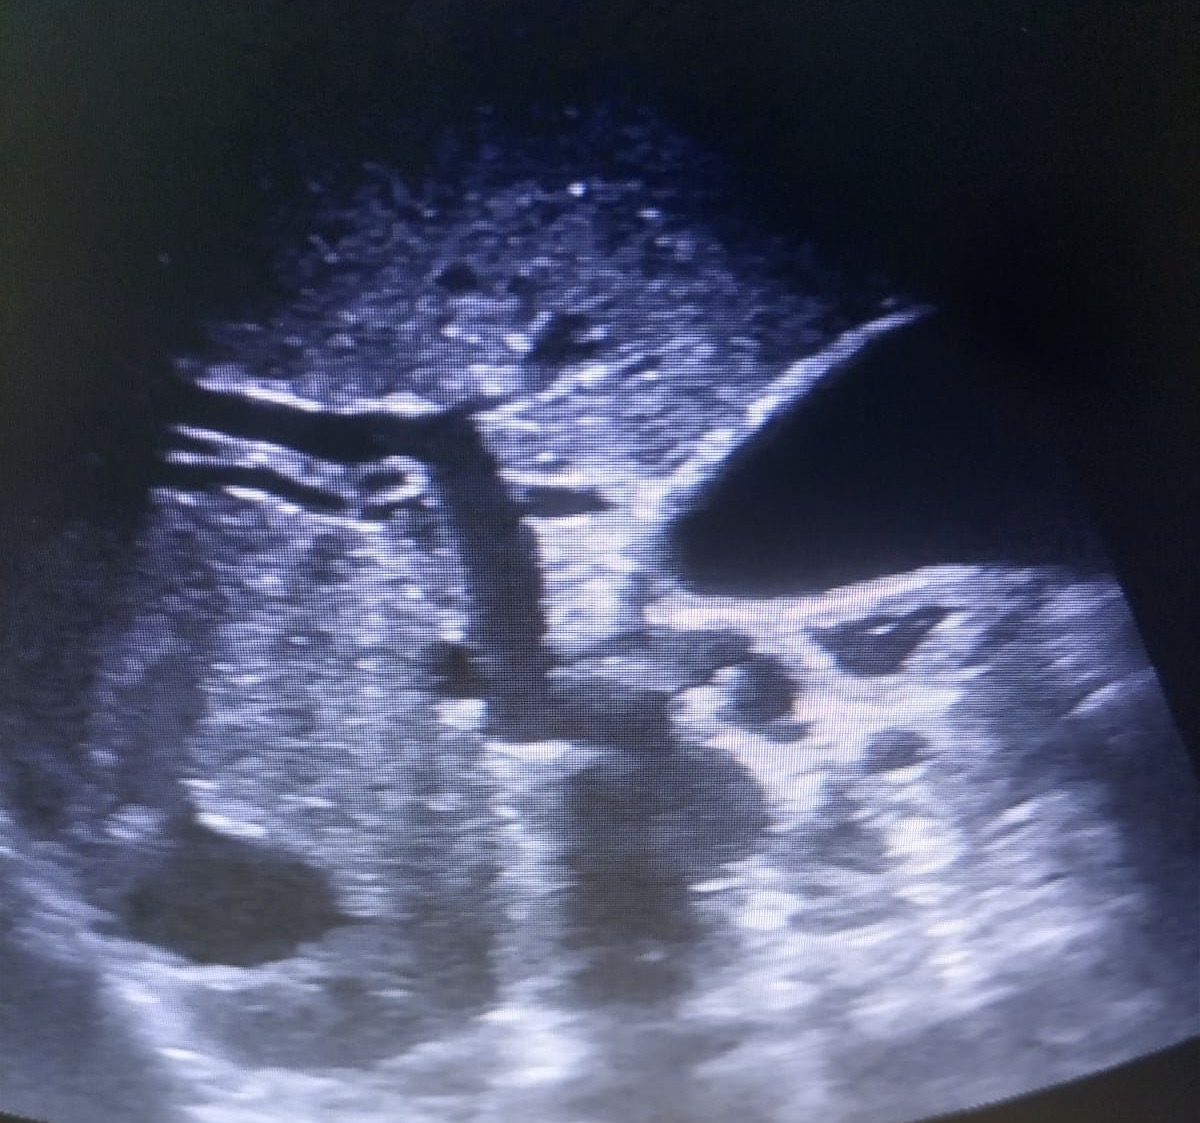

Hallazgos ecográficos

Observamos una lesión a nivel de la cabeza del páncreas, de bordes mal definidos, hipoecogénica, además de dilatación del conducto de Wirsung y dilatación de la vía biliar tanto intra como extrahepática.